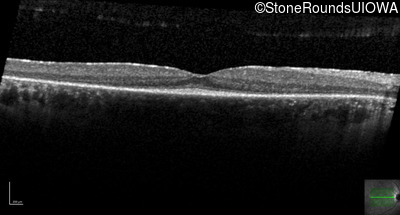

Optical Coherence Tomography - Right -

20/20 -1

Exemplar / OCT Stack